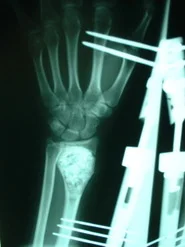

Paciente del sexo femenino de 15 años de edad, portadora de Quiste Óseo Aneurismático de radio derecho, quien había sido intervenida hace aproximadamente 1 año en otro centro, donde le practicaron curetaje de la lesión y relleno del quiste con injerto de cresta ilíaca. La lesión recidiva, acude por la consulta del Dr. Alberto A. Martínez Conde, donde previa revisión de las laminas histológicas por parte del Dr. David Mota, se practicó curetaje amplio del quiste y relleno de la cavidad con Hidroxiapatita sintética e injerto de cresta ilíaca, se estabilizo el radio con tutor externo.

El resultado post-operatorio con seguimiento de 1 año fue excelente, sin signos de recidiva